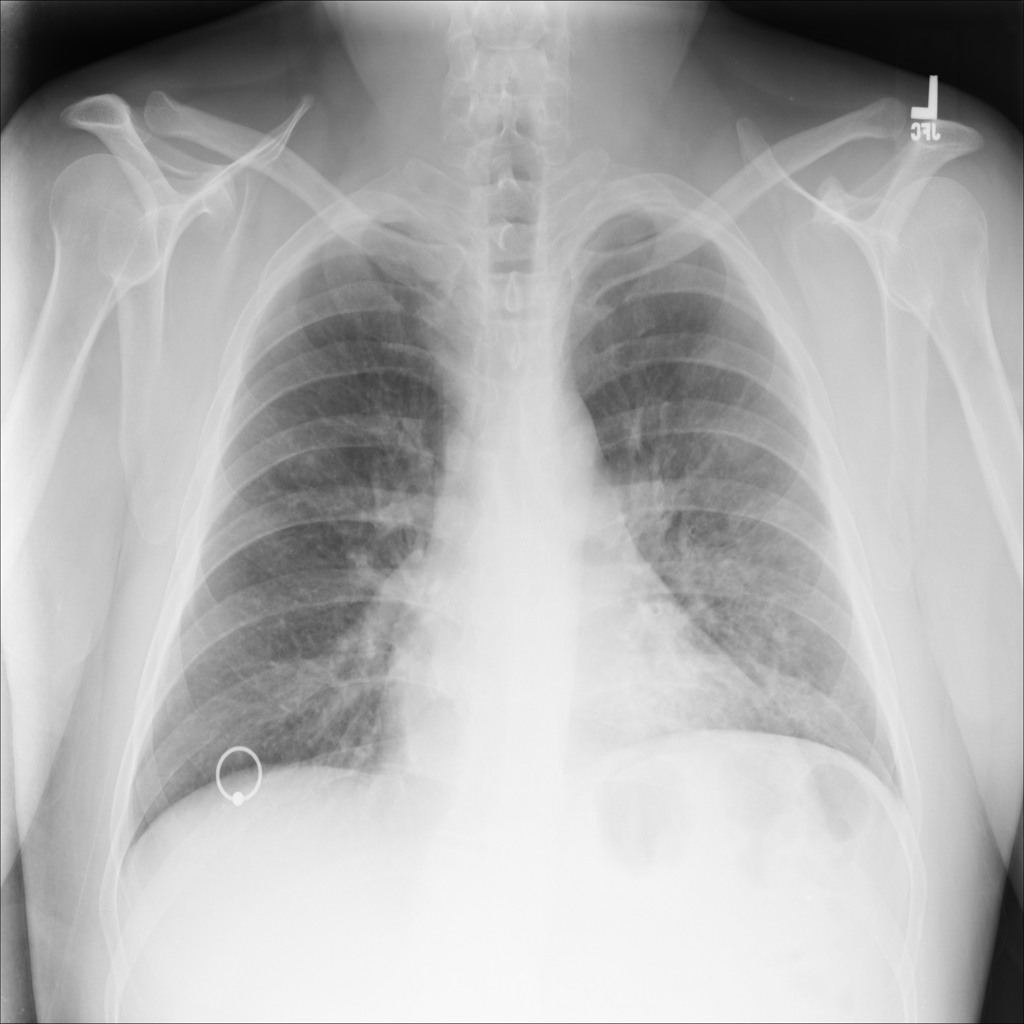

PAT-B3C3 · IMG-001Pneumonia

PAT-B3C3 · IMG-001

PA